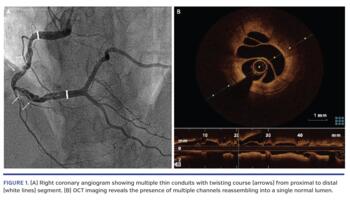

A 52-year-old female was referred to our catheterization lab due to chest pain and stress-induced myocardial inferior ischemia. Coronary angiography revealed an abnormal segment of the right coronary artery (RCA); its lumen was divided into thin channels with a twisting course reassembling into a single normal lumen in the distal segment of the RCA with TIMI 3 blood flow (Figure 1A; Video 1). Optical coherence tomography (OCT) was performed to confirm the presence of a woven coronary artery anomaly (WCAA) (Figure 1B). The similarity of the angiogram to the braided hair gives the name to this entity. WCAA was first described in 1988, and a limited number of cases have been reported since then. Most patients are adult males and the affected vessel is usually the RCA. The etiopathogenesis is still unclear; it is probably a congenital malformation, although some authors have suggested that recurrent spontaneous dissections could be responsible.

WCAA has been considered a benign pathology, as it was usually incidentally detected. However, cases with ischemia, infarction, and arrhythmia are increasing. Recognition is difficult because of its rare nature. Moreover, it can be misinterpreted as recanalized thrombus, spontaneous coronary dissection, or chronic occlusion with bridging collaterals. OCT imaging is challenging due to the tortuosity of the channels. However, it is crucial not only for the differential diagnosis but also to guide the approach. This patient was successfully managed with optimal medical treatment.